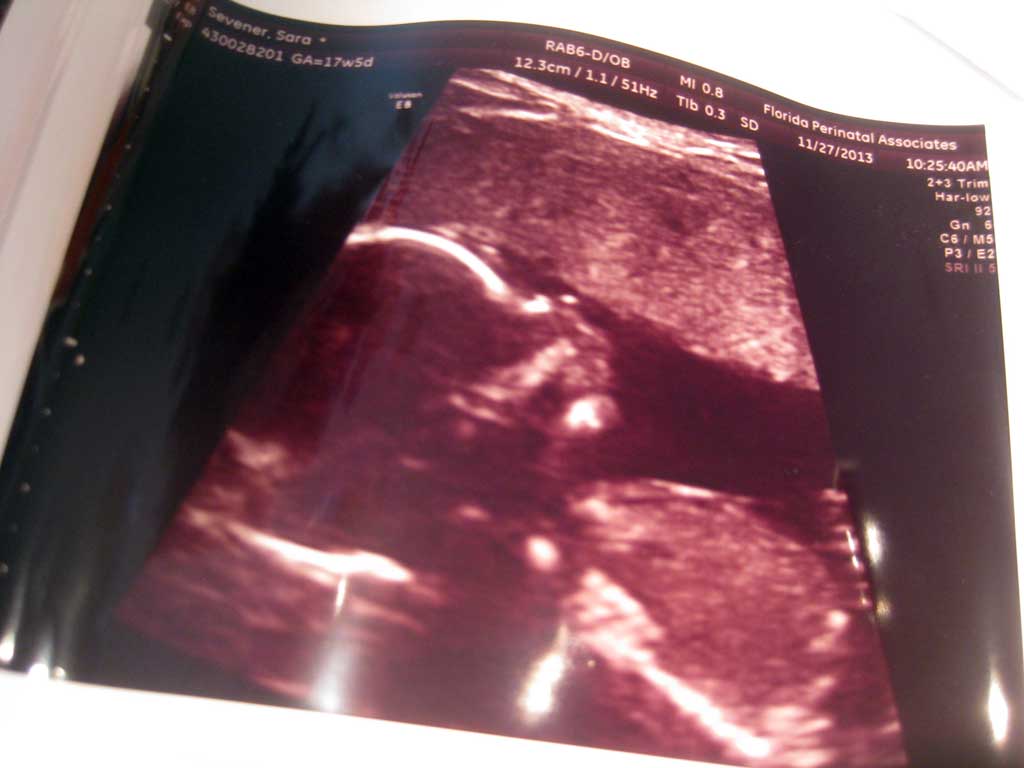

…which is why technically our son was first conceived in a test tube a year ago February, but ended up spending six months on ice before he was thawed and put back in with crossed fingers last August…

- I learned a lot about cellular biology, and I’ve got a picture of my son when he was only 32 cells old that few people can beat!

I mean, even now I still worry a little in the back of my head – when are we going to get to bring Christopher home and what are we going to hear that might be bad from the next status update???